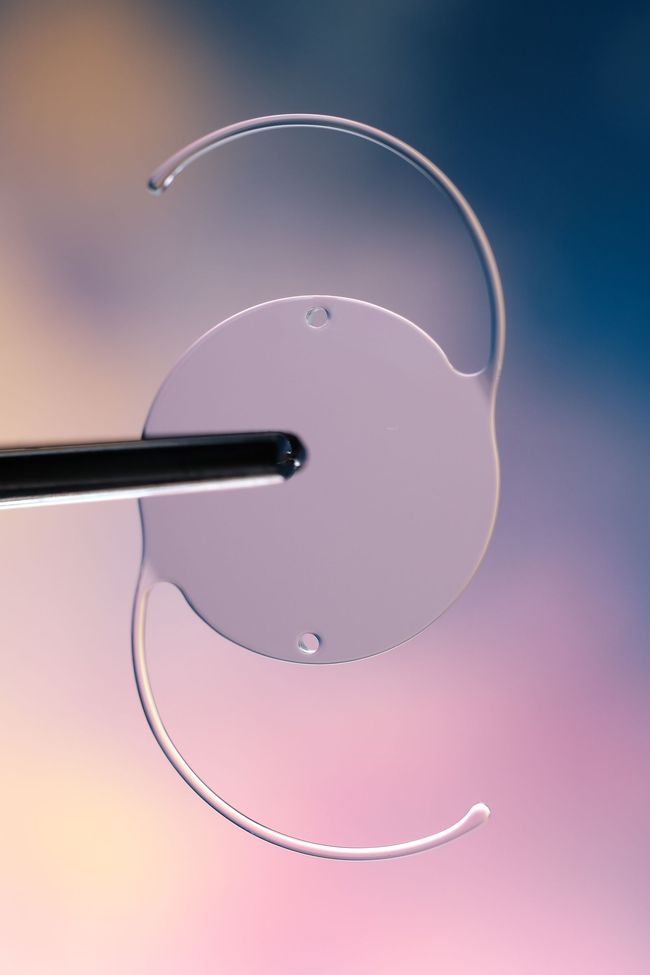

Implante de lente intraocular.

Contamos con diversas opciones de lentes intraoculares diseñados para restaurar la visión después de una cirugía de catarata o corregir defectos refractivos. El procedimiento se realiza con precisión y bajo control tecnológico avanzado.